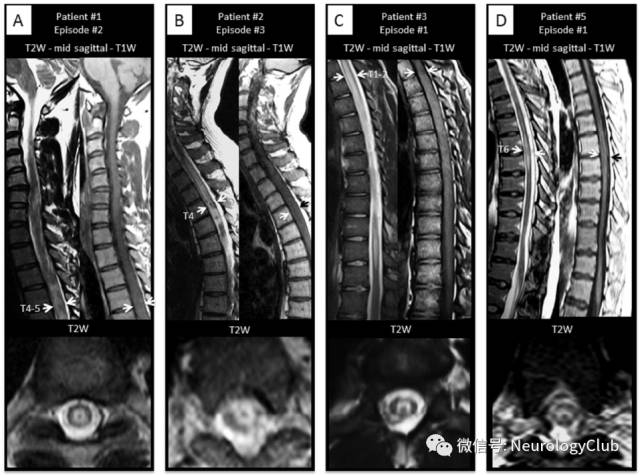

脊髓受累

(图27:NBD患者脊髓受累;A:T2WI可见全脊髓多发高信号病灶;B:增强后可见片状强化;C:治疗后病灶基本消失)

(图28:长节段脊髓受累的NBD患者;A:T2WI可见脊髓T3-L2异常信号;B:增强后病灶强化;C:10月后复查可见局部胶质增生不伴强化)

(图29:长节段脊髓受累的NBD患者T2WI横断面可见“百吉饼征”,或与静脉怒张有关,可能为其特征性影像,有助于与其他长节段脊髓病变,如视神经脊髓炎谱系疾病等鉴别

鉴别诊断